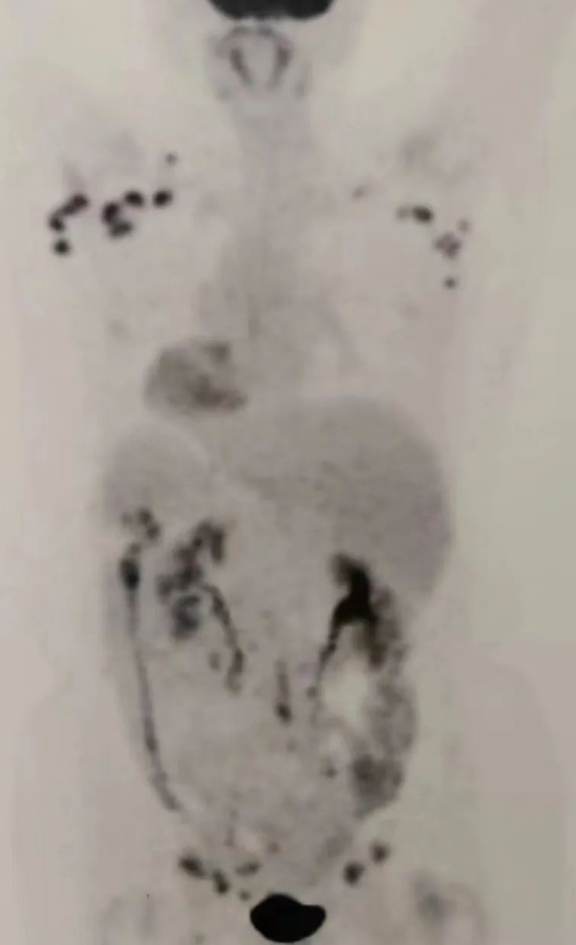

图片上黑色分布区域为肿瘤病灶。来自肿瘤组织的杀敌利器

2021年7月9日 吴霞芳回国后接受治疗前进行PET-CT全身评估,转移灶遍布全身,包括腋窝淋巴结、锁骨淋巴结、子宫、双侧附件、腹膜、盆腔、腹股沟淋巴结等。